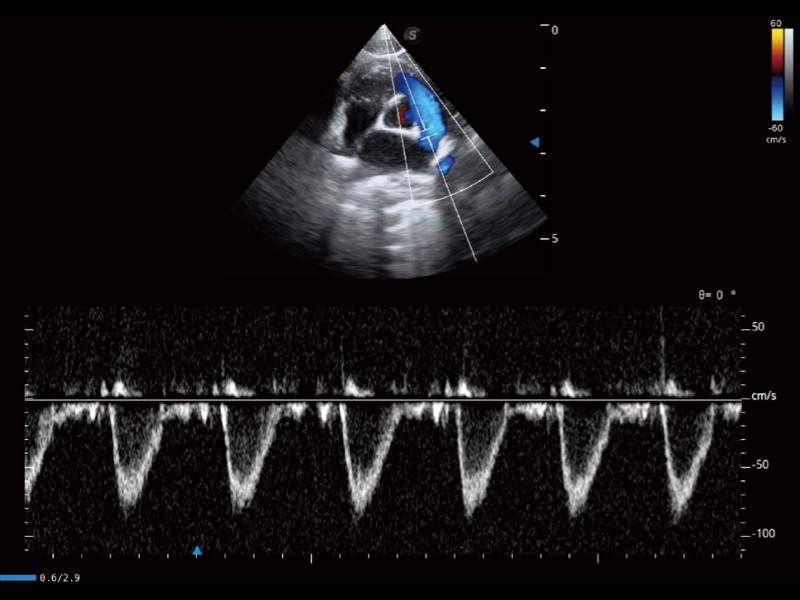

通过创新的 Matrix E自适应滤波器和超长时间域算法,极大提升超低速微细血流的检出能力,同时更精准地滤除软组织和噪声信号,为兽用医生提供以往无法通过常规血流获得的疾病诊断信息。